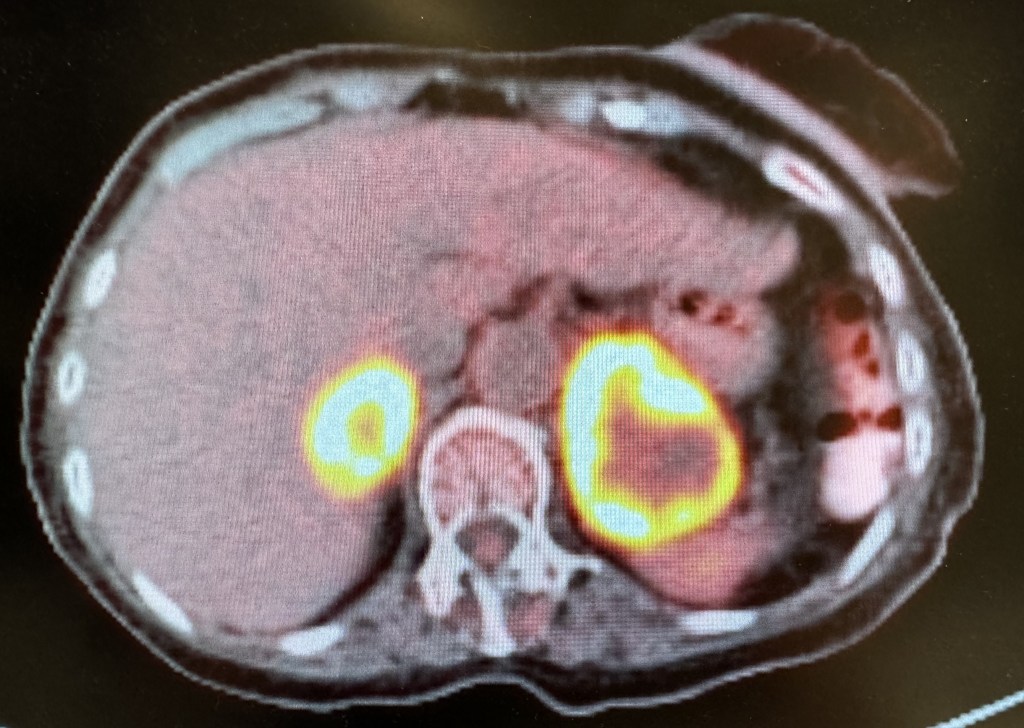

Böbrek üstü bezlerinin metastazlarında veya tanı konulması gereken diğer durumlarda başvurulan sürrenal (adrenal) biyopsi tomografi eşliğinde gerçekleştirilmektedir. Aynı gün taburculuk yapılabilmektedir.